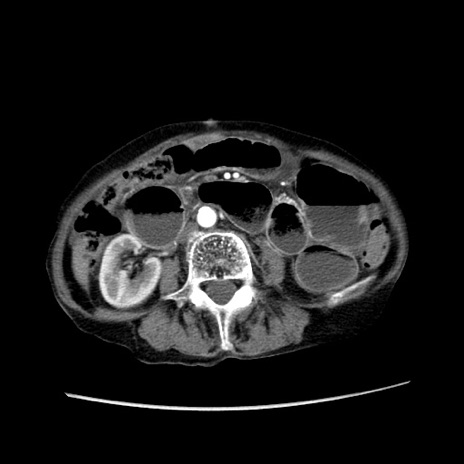

症例25(横断像)

【症例】80歳代女性

【主訴】胸のつかえ感

【現病歴】約9時間前に食後から胸のつかえた感じあり、嘔吐あり、来院。

【既往歴】胃癌(全摘)、胆摘、虫垂炎

【身体所見】心窩部に圧痛あり、反跳痛なし。

【データ】WBC 5700、CRP 0.05